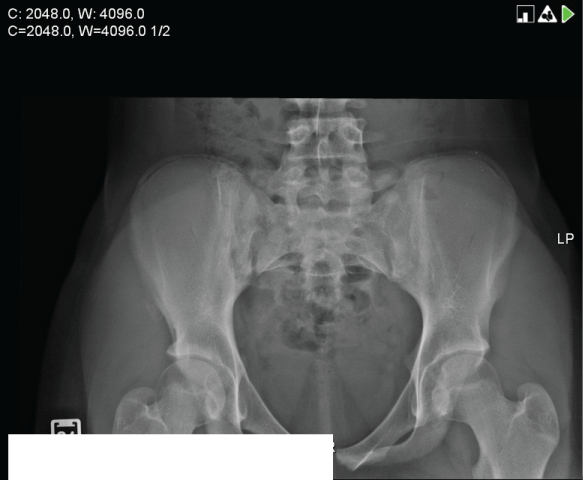

A 13 year-old female presented to the Emergency Department (ED) with a one-day history of right hip pain after participating in mosh pit activities. She denied any past medical history of right hip pain, direct trauma or fever. Vital signs were as follows: Temperature 36.88°C (98.4°F), heart rate 66 beats/minute, blood pressure 122/70mmHg, respiratory rate 18 breaths/minute and oxygen saturation 99% room air. In the ED she was limping. Physical examination revealed tenderness over the anterior iliac crest. Active range of motion of the right hip was limited due to pain. The remainder of the examination was unremarkable. A radiograph of her pelvis revealed an avulsion fracture of the right anterior superior iliac spine (Figure 1).